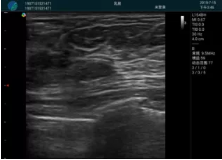

可視化穿刺引導(dǎo)

M20實時引導(dǎo):向包塊后方間隙注射利多卡因

清晰顯示腺體內(nèi)低回聲快影,邊界清晰,包膜較光滑

確定進(jìn)針路徑并實時監(jiān)測抽吸針與腫塊位置關(guān)系

抽吸針進(jìn)入腫塊內(nèi)部進(jìn)行旋切

抽吸過程中可見腫塊明顯縮小,并根據(jù)腫塊位置改變針道位置

抽吸旋切后再進(jìn)行超聲復(fù)查,原腫塊區(qū)域未見殘留組織及出血

超聲引導(dǎo)下抽吸旋切取出的腫塊組織